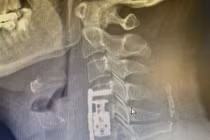

10 năm bị thoát vị người bệnh bị chèn ép tủy cổ, tê bì và yếu hai tay....sau thay khớp đã vận động tốt. Phẫu thuật cần được tiến hành sớm tránh những biến chứng và mang lại chất lượng cuộc sống tốt hơn cho người bệnh.